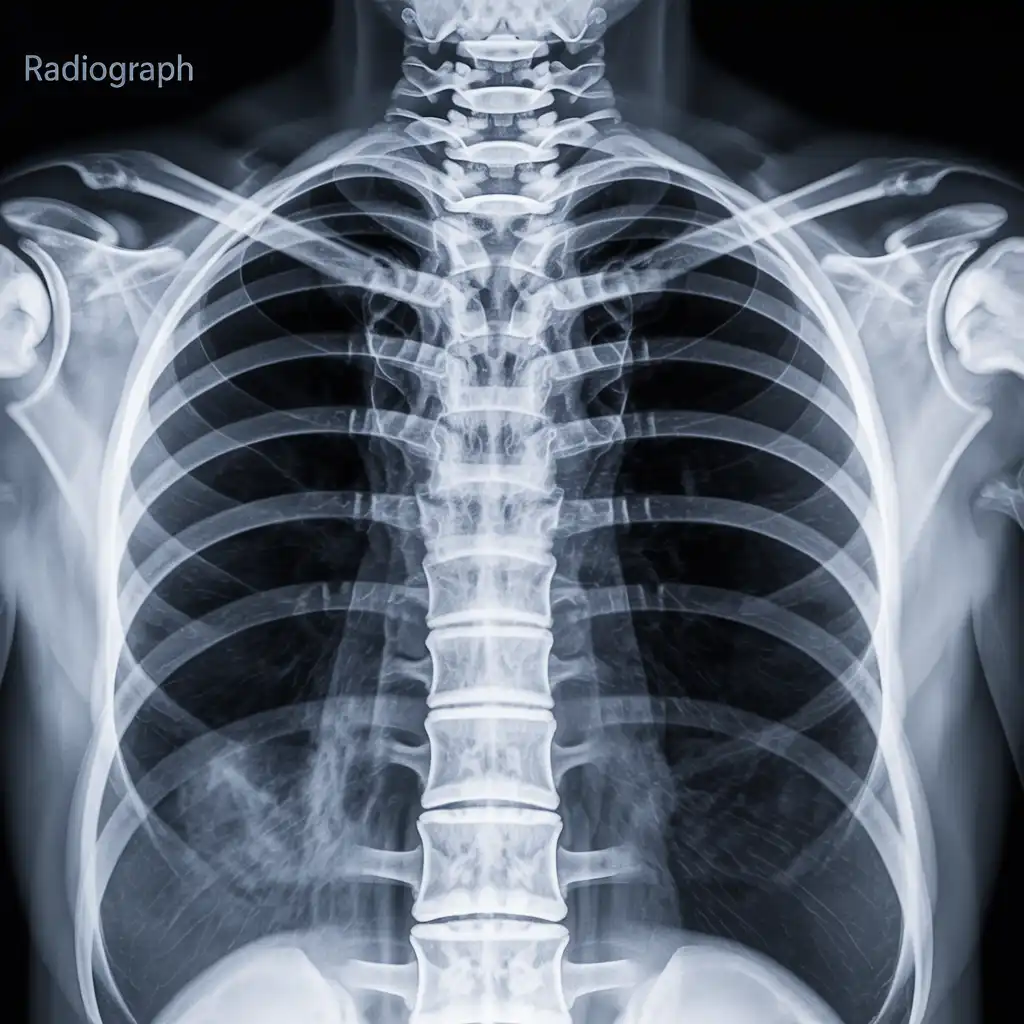

Da anni offriamo un servizio di radiografie a domicilio pensato per garantire ai nostri pazienti la stessa qualità diagnostica degli esami eseguiti in ospedale, ma con la comodità e la sicurezza della propria casa.

Abbiamo effettuato migliaia di esami direttamente presso abitazioni, residenze e strutture assistenziali, utilizzando apparecchiature digitali portatili certificate e procedure rapide e sicure.